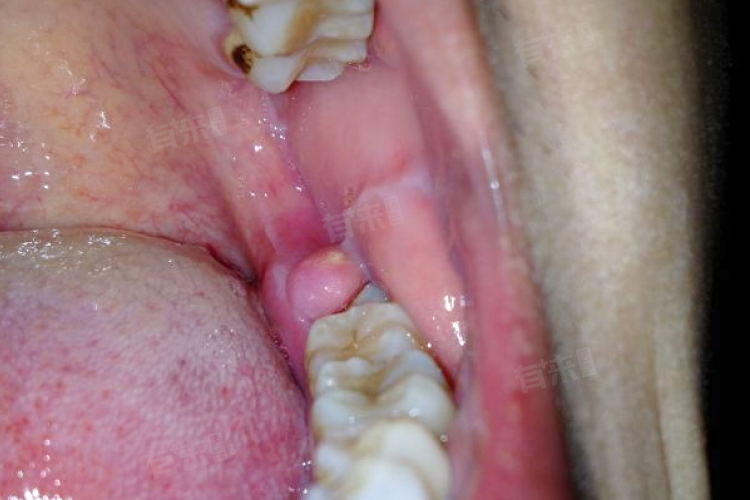

智齿萌出处的牙龈有时会出现红肿现象,颜色变得比正常牙龈更红。这是因为智齿在牙槽骨内生长,对牙龈产生了一定的挤压和刺激,使得牙龈出现了炎症反应。

部分人在智齿萌出前,对应的牙龈处容易反复出现炎症。表现为牙龈红肿加重、疼痛变得明显,还可能伴有少量的出血,严重时甚至会出现低热等全身症状。